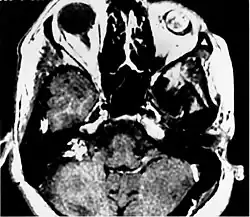

Imaging studies help to identify the tumor and the specific anatomic site of involvement. Magnetic resonance images show a hyperintensity (hypervascularity) of a heterogeneous mass by T1 weighted images. Computed tomography shows a multilocular, lytic destructive temporal bone mass, centered on the vestibular aqueduct (between internal auditory canal and sigmoid sinus).[1][6][7]